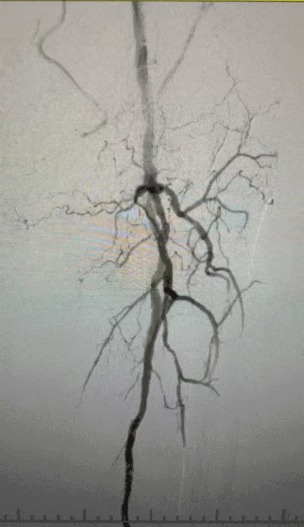

Approche de traitement

Compte tenu de l'état vasculaire complexe, nous avons sélectionné le système de cathéter de dilatation à ballonnet IVL périphérique ThorCrack. En raison de la tolérance limitée du patient, des procédures interventionnelles par étapes sur les deux membres inférieurs ont été réalisées.

Résultat chirurgical

Après la procédure, la sténose artérielle s'est améliorée de manière significative, le flux sanguin a augmenté et la température de la peau a augmenté. Aucune complication postopératoire n'est survenue. Le patient et l'équipe chirurgicale étaient très satisfaits des résultats.